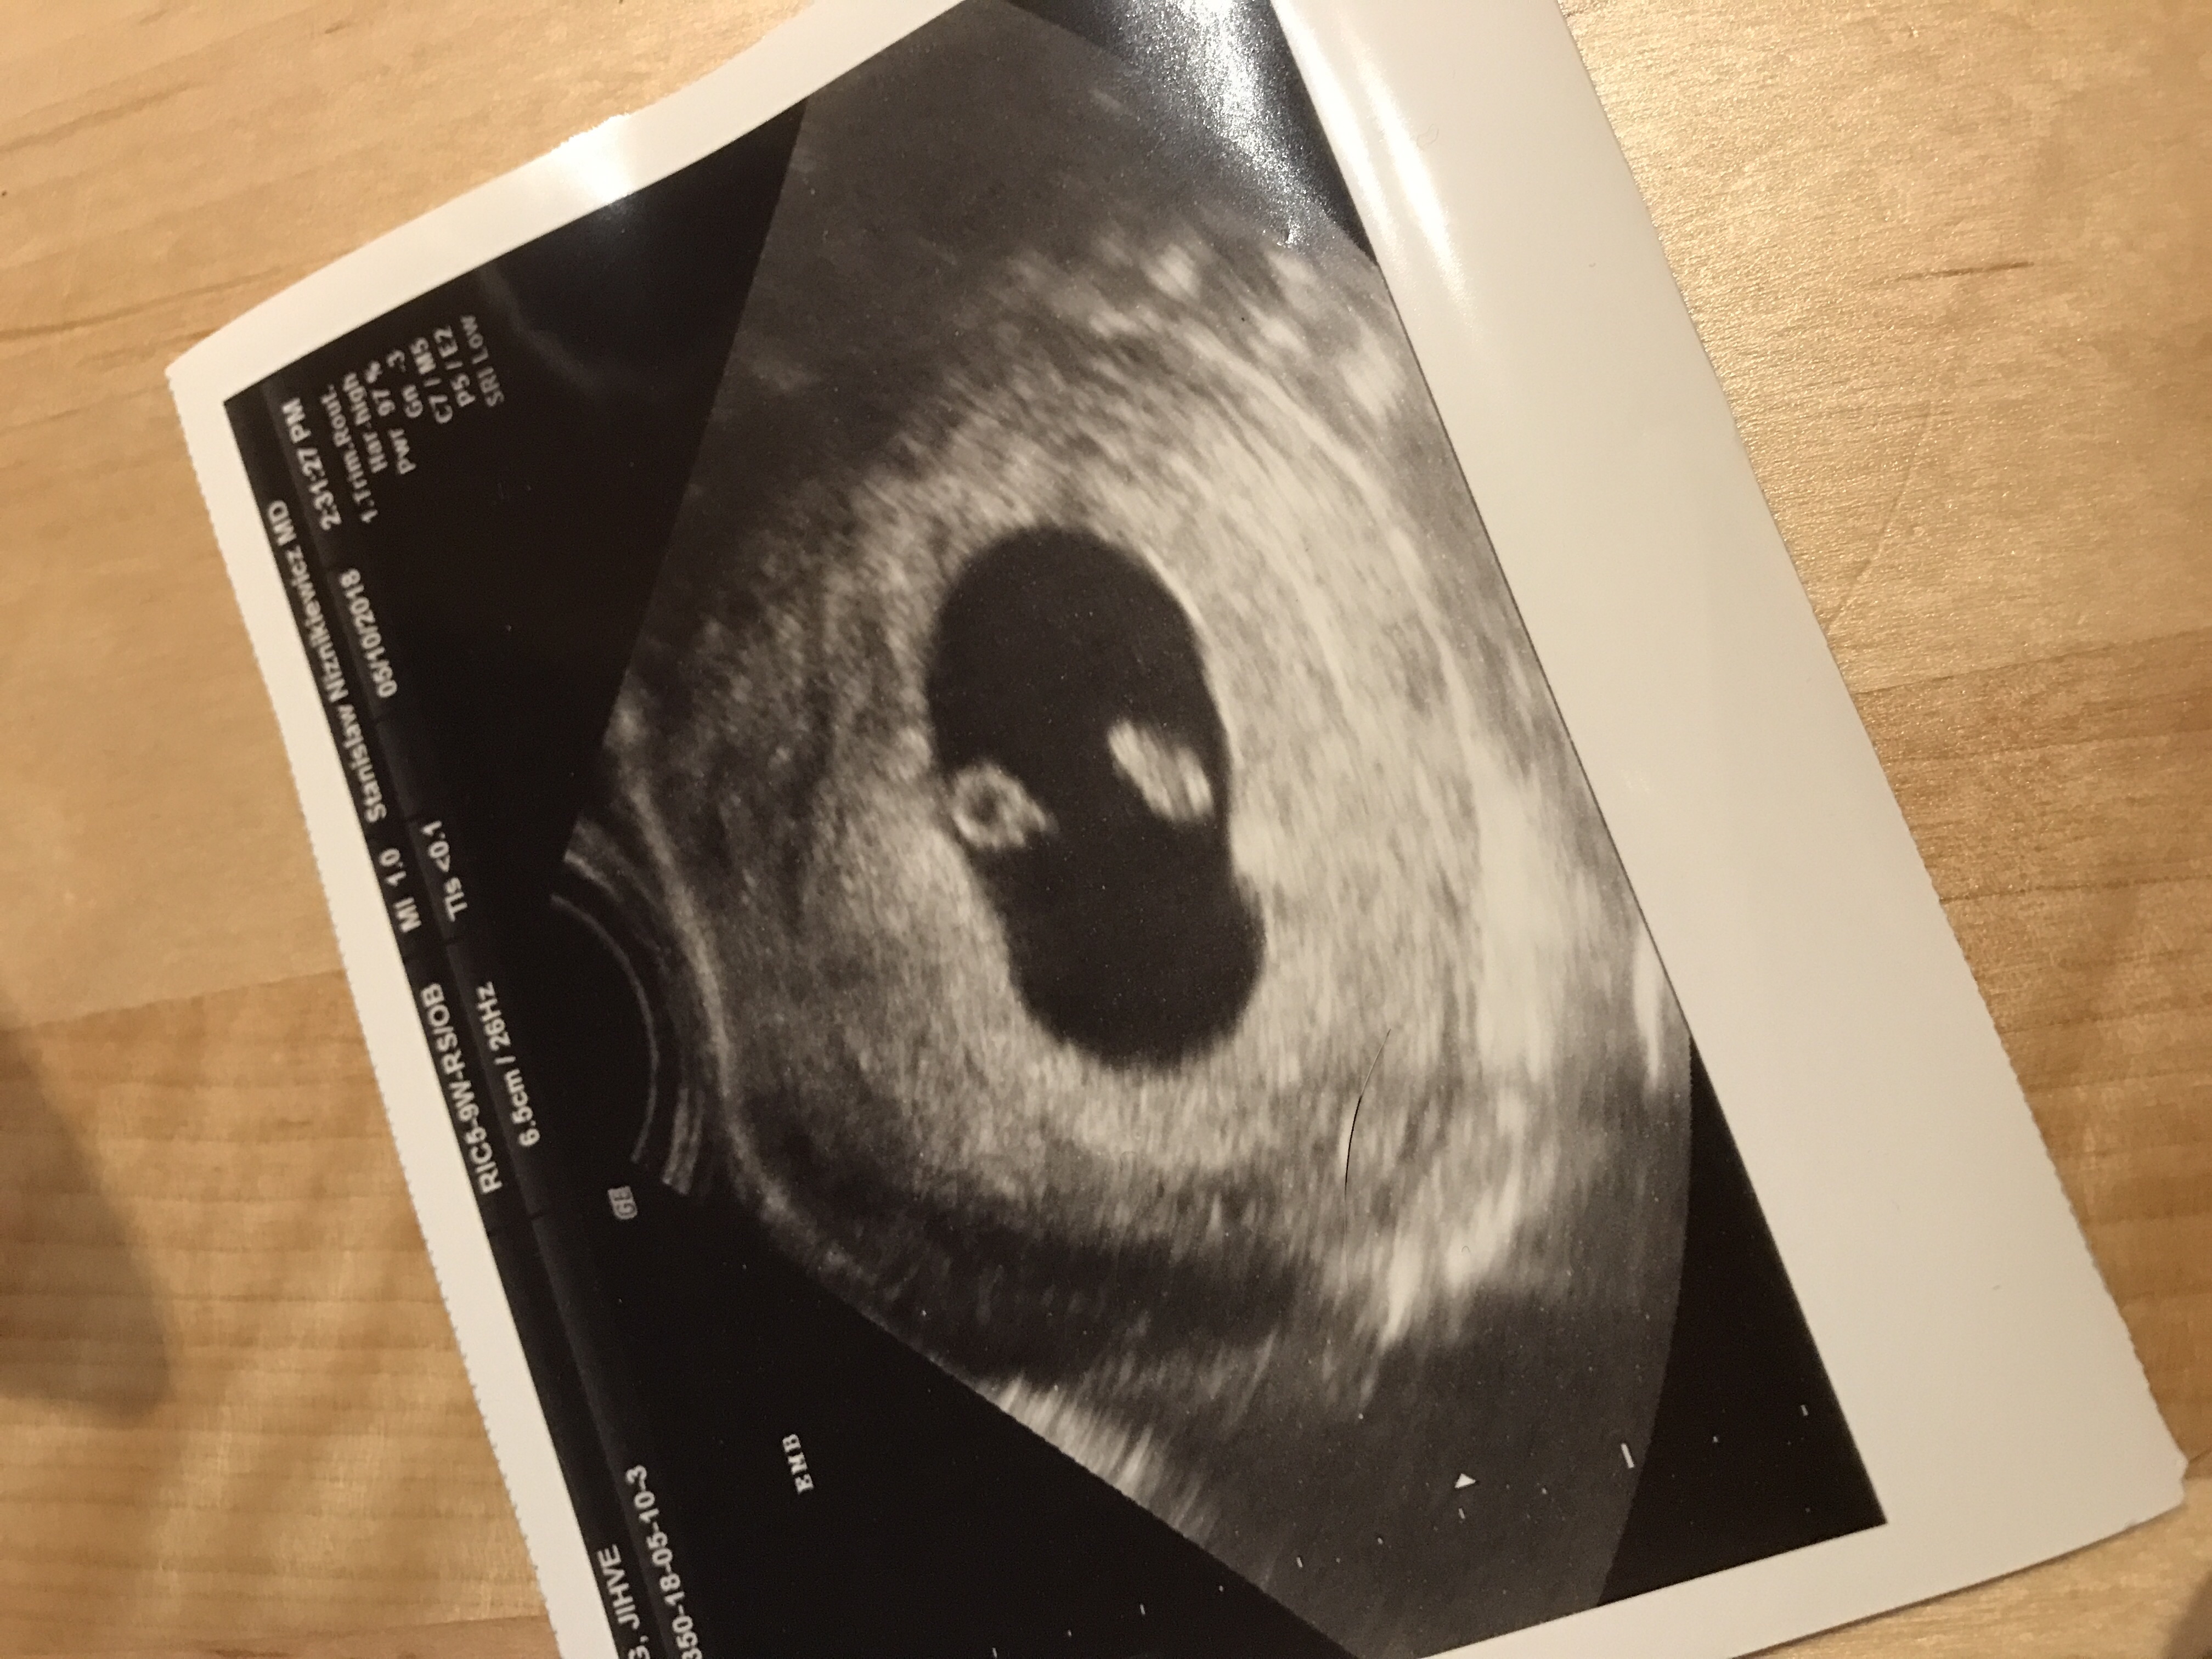

͏°´õ »ó¿¡´Â 7ÁÖ 2ÀÏÀε¥ ÃÊÀ½ÆÄ·Î´Â 6ÁÖ 5ÀÏÀ̶ó³×¿ä~

À§¿¡°¡ ³È²ÀÌ°í ¾Æ·¡°¡ ¾Ö±âÀε¥..

¿ø·¡ Àú·¸°Ô ¶³¾îÁ®Àִµ¥ ¸Â³ª¿ä? ÃÊÀ½ÆÄ ¿µ»óÀ¸·Î ºÃÀ»¶§´Â ¹º°¡ Áß°£¿¡ ±æ´Ù¶þ°Ô ¼±ÀÌ Àִ°Š°°´øµ¥ ÅÈÁÙÀ̶ó±â¿£ ³Ê¹« À̸¥°Å°°°í..

ÀÇ»ç½ÜÀº ¾Æ¹«·± ¹®Á¦ ¾ø°í ¾ÆÁÖ ÁÁ´Ù°í ¾ê±â´Â ÇϽôµ¥

½ÉÀåµµ ÀÌÁ¦ ¸· ¶Ù±â ½ÃÀÛÇØ¼ ¾ÆÁ÷Àº ¾àÇÏ´Ù°í ÇÏÁö¸¸ Á¤»óÀ̶ó°í ÇϽôµ¥.. ÁÖ¼ö¿¡ ¸Â°Ô Àß Å©°íÀִ°ÇÁö..